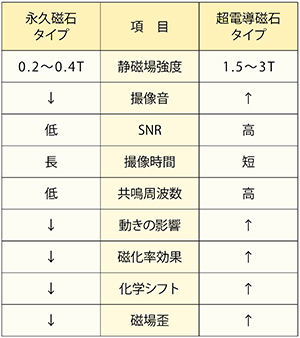

2.静磁場強度の「違い」(表2)

次に,静磁場強度の違いでどのような影響があるかを整理します。表2に示すように,静磁場強度によりさまざまな項目が影響を受けます。

表2 永久磁石タイプと超電導磁石タイプの違い:

静磁場強度